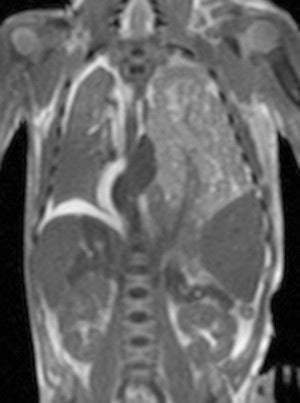

The large, double-blinded prospective study compared conventional autopsy with the diagnostic accuracy of noninvasive, cerebral postmortem MRI, specifically for cerebral and neurological abnormalities in fetuses and children. The research team found postmortem MRI is accurate for identifying significant neuropathology in fetuses and children, and it may provide vital information even in cases in which formal neuropathological examination cannot occur (Clinical Radiology, 4 June 2015).

The researchers of the current study performed preautopsy cerebral postmortem MRI in a sequential, prospective cohort of 400 fetuses and 123 children younger than 16 years of age. Postmortem MRI and conventional autopsy findings were reported blinded and independently of each other.